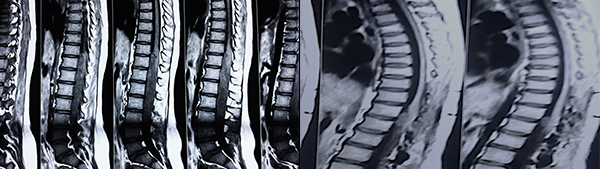

Es evidente que el límite entre el tejido medular y tumoral en las lesiones como los astrocitomas es indiscernible lo que dificulta la posibilidad de resección completa; en los tumores como los ependimomas esta diferencia es más franca y permite seguir un plano de disección seguro (Figuras 3, 4 y 5). Lo anterior condiciona nuestros resultados como han puntualizado diversos autores.5,8 El estado general previo a la cirugía requiere de una valoración juiciosa de las posibilidades de resección. Por ejemplo, el caso 12 (Figura 6) es una paciente portadora de Enfermedad de Von Hippel Lindau, Hemangioblastoma cervical biopsiado en otra institución del exterior del país, fijación de columna cervical y sindrome de Cushing por exceso de medicación corticoidea cuya cirugía debió suspenderse en dos oportunidades por la disminución de su capacidad ventilatoria. Con estos antecedentes y la delgada capa de tejido medular evidenciada intraoperatoriamente se optó por una resección subtotal. A los cuatro meses de la cirugía la paciente recuperó la marcha autónoma y demás parámetros clínicos.

Figura 3: Caso 10. Ependimoma cervical pre operatoria: Lesión sólida C3 y dilatación siringomiélica. Posoperatorio: resección completa, disminución de la cavidad. Restos hemáticos decantados.

Respecto del monitoreo intraoperatorio, la utilidad del registro de potenciales evocados, Onda D o Electromiografía dependerá no solo de la obtención de respuestas sino también del diálogo entre el cirujano y el neurofisiólogo,11-13 debido al fenómeno de falso negativo y positivo como se muestra en la Tabla 4. El cirujano recibe la información con retraso al evento y en ocasiones las maniobras de “reanimación” medular (irrigación con suero tibio, corticoides, etc.) no son concluyentes produciendo el abandono de una resección factible. La laminoplastía busca favorecer la restitución del alineamiento espinal, pero debe mantenerse un control, en particular en tumores de la unión cérvico dorsal, sobre el desarrollo o acentuación de escoliosis (Figura 3), en ocasiones presente al diagnóstico y que se acentúa en la evolución posoperatoria.13,16